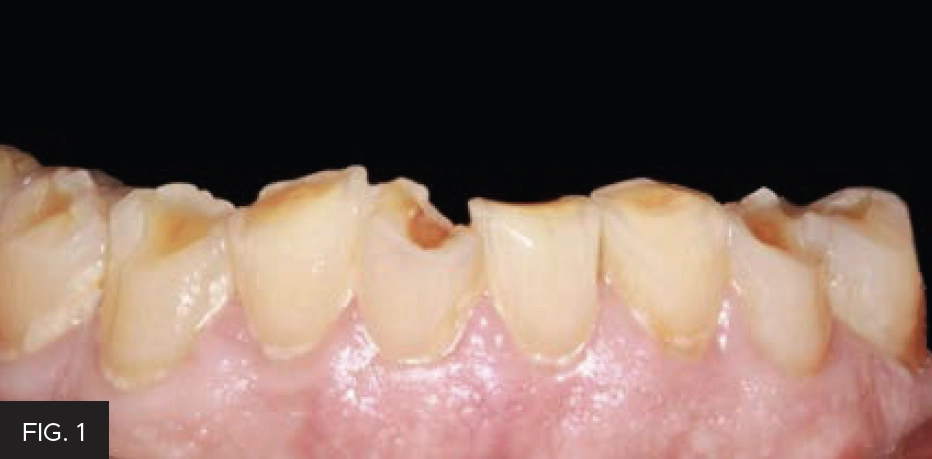

Having the capability to quickly and predictably transfer a mock-up into a patient’s mouth using composite resin allows clinicians to offer their patients alternative treatment options. This procedure provides an effective way to restore multiple teeth in the arch as temporary, transitional and/or permanent restorations. (FIG. 1)

After the first set of teeth were restored, finished with Neodiamond pointed cone bur (ref #3314.10VF) and polished with ceramic polishing wheels: coarse blue (FLW14C), medium pink (FLW14M), and fine gray (FLW14F), the same procedure was done to restore #’s 22, 24 and 26. Finally, the occlusion was adjusted to achieve bilateral simultaneous equal-intensity contacts.